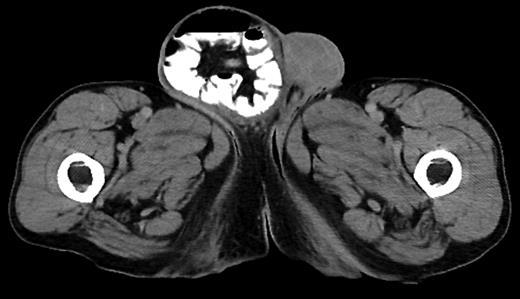

A 62-year-old male with bloody diarrhea was referred to surgery for management of duodenal mass. Evaluation by EGD, computed tomography (CT) imaging and elevated chromogranin indicated a possible neuroendocrine tumor. Further exam revealed umbilical and large right-sided inguinal hernia.

The patient was taken for elective laparoscopic possible open surgery, and pneumoperitoneum was created using a Veress needle. Three 5 mm trocars were placed: one on the midclavicular line below the right and one below the left costal margin, third in the anterior axillary line at the left costal margin, and a 15 mm trocar was placed in the midline, through the large umbilical hernia defect. Intraoperative endoscopy-assisted resection of the tumor was done extending from the gastric incisura to beyond duodenal bulb with clear margins and placed in the endopouch and moved intracorporeally toward the planned hernia incision site and left in situ, then antecolic antegastric Gastrojejunostomy was performed and Petersen's defect closed.

A 6 cm incision 2 cm superior to the right pubic tubercle was made, large indirect sac was found, dissected free of the cord and suture ligated. Lichtenstein procedure was performed for the repair of the defect. At this time, the tumor specimen placed in the endopouch was removed via hernia orifice.

Finally, the umbilical trocar was removed, and the umbilical hernia defect was repaired. Total surgical time was 105 min, blood loss estimated at <25 ml. Postoperative period was uneventful. Patient was discharged after 3 days with no complications. Pathological finding confirmed Grade I well-differentiated neuroendocrine tumor involving the mucosa and submucosa of the duodenum with foveolar metaplasia. After 2 years of regular follow-up with surgery, hematology and oncology, CT and octreotide scan for neuroendocrine activity, there has been no sign of further recurrence of the tumor.